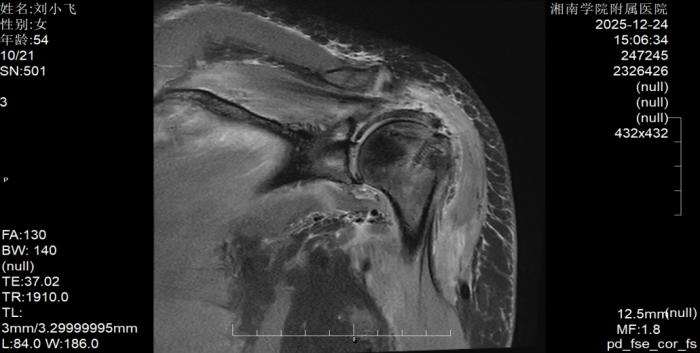

据了解,患者刘阿姨因左肩部疼痛辗转求医多日,尝试吃药、针灸、推拿等多种治疗后症状不仅未改善,反而持续加重,最终发展到无法端碗吃饭、自行穿衣洗澡的程度。转诊至江南娱乐网址登录 后,经术前MRI检查确诊为巨大肩袖撕裂,且肩袖缺损范围大、肌腱质量差,传统修复方式难以达到理想效果。